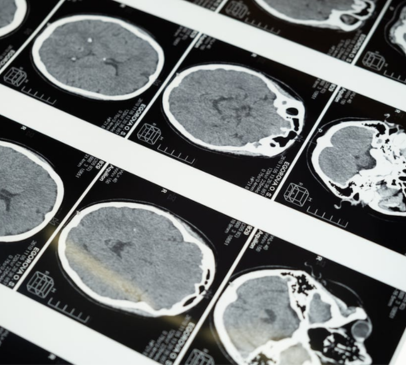

Traumatic brain injury (TBI) has been discussed as one of 14 risk factors contributing to dementia risk in a new 2024 Lancet Commission, Dementia prevention, intervention, and care: 2024 report of the Lancet standing Commission.

TBI is discussed as continuing to be a risk factor for dementia, with new evidence suggesting that protection from head injury through contact sports should be an individual and public health priority, for which ambitious policy changes should be made at national and international governmental levels.

The commission offers an overview of key research studies conducted on the topic of TBI in sports, concluding that TBI increases dementia risk, possibly leading to earlier onset of dementia by 2 – 3 years than in non-TBI populations. A number of plausible underlying neuropathologies are suggested. Protection from head injury in sports is recommended to be an individual and public health priority, for instance by introducing appropriate head protection equipment, limiting heading practice and high-impact collisions, preventing playing immediately after TBI and possible adaptations of rule changes to limit injury.